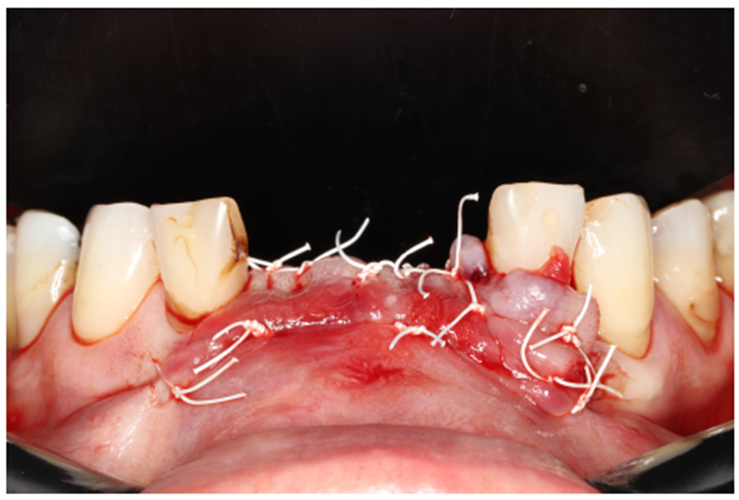

Paciente RV, do sexo masculino de 52 anos, compareceu a nossa clínica com queixa estética e funcional dos dentes incisivos centrais superiores. No exame clínico observou-se doença periodontal severa com presença de bolsa periodontal e perda óssea marginal maior do que 7 mm (Figura 1). Foi realizado em nossa escola (Beo – Ensino Odontológico Avançado) uma tomografia computadorizada para melhor planejamento cirúrgico do caso, onde confirmamos a necessidade de regeneração óssea guiada com membrana Cytoplast com reforço de titânio, devido à perda óssea vertical maior do que 7 mm (Figura 2). Após definição do planejamento cirúrgico, foi realizado a exodontia dos incisivos centrais superiores, limpeza cirúrgica da região e osteotomia periférica para melhor preparo do leito receptor do material de enxertia de lenta reabsorção Bio-Oss (Geistlich) e da membrana Cytoplast com reforço de titânio 30 mm X 40 mm (Figuras 3,4 e 5). Após estabilização da membrana, foi realizado a sutura com fio do tipo Cytoplast 3.0 mm devido a sua alta plasticidade, diminuindo o risco de deiscência de sutura (Figura 6).